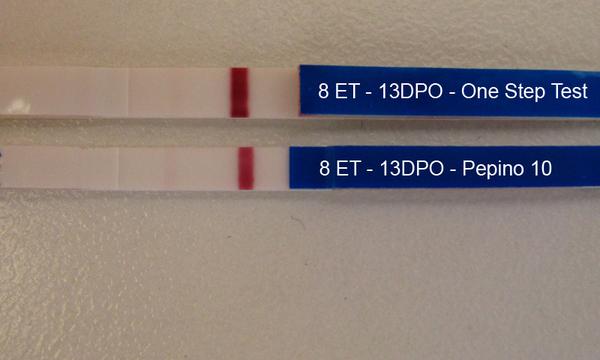

@dadenka111 Dušík je stále vidět a řekla bych, že je o malinko silnější než včera 🙂

@dadenka111 Já vidím rozhodně duch ajsněji než včera, to je dobré znamení 🙂 Velká gratulace, je to skvělý 🙂

@dadenka111 super, taky si myslím, že je silnější, než včera 🙂